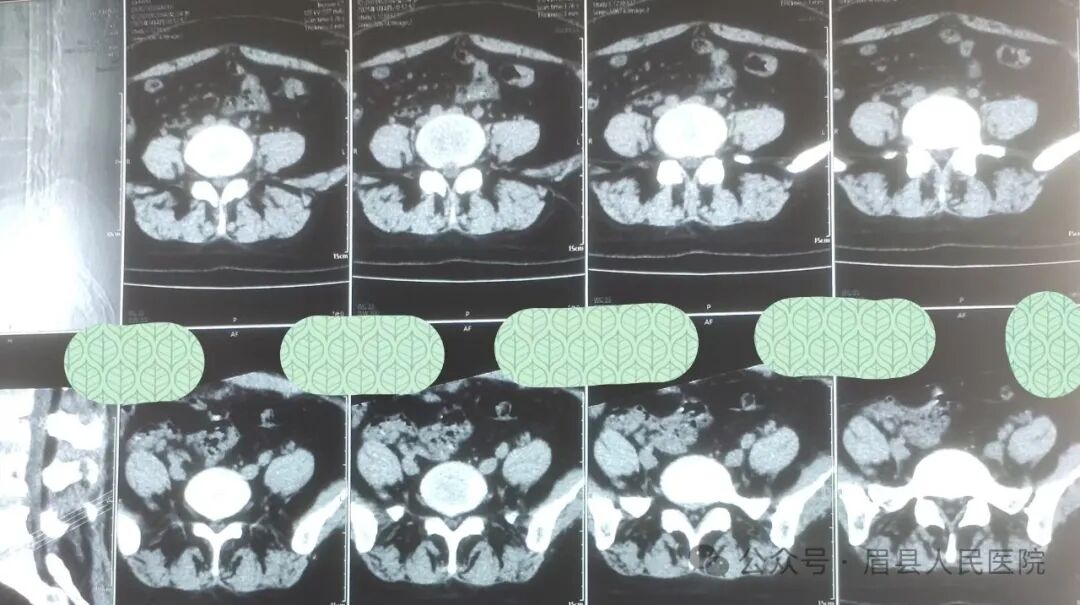

近日,眉县人民医院疼痛科接诊了一位特殊的患者。一位 34 岁产后女性患者于一周前突发腰疼,在其他医院进行 CT 检查后,被诊断为腰椎间盘突出,经口服外用药物后,治疗无效,疼痛依旧剧烈,且双肩严重不等高,脊柱呈严重的 S 型侧弯。前几日,又前往某中医院治疗,效果仍不理想。